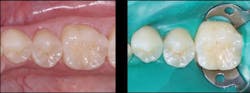

Figure 4: Final prep (left) and acid placed for selective etch of enamel only (right). Liner was not placed in this prep. Etch-and-rinse (total-etch), selective, and self-etch techniques have been shown to be adequate.

Figure 5: Glutaraldehyde placed for two one-minute applications and suctioned off (left) followed by your choice of bonding agent (right)

Figure 6: Finished restoration. Restorations accomplished in this manner will not have postoperative tooth sensitivity.